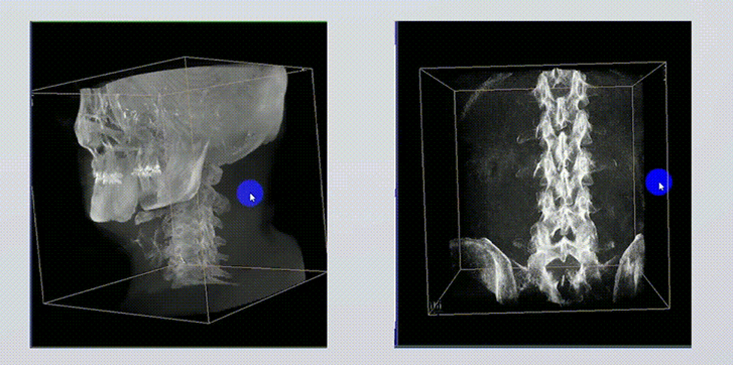

1、术中实时三维成像

术中三维成像和横断面图像提供多角度的手术诊断信息,辅助医生进行术中评估判断,诸如骨折复位情况和内植入螺钉的尺寸和位置,辅助手术更好地完成。

提供更大的术中三维成像视野,采集更多图像信息,可一次拍全全段颈椎、全段腰椎、七节胸椎、双侧骶髂关节、股骨头及单侧盆骨。